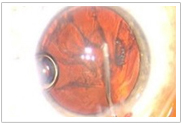

手術(shù)醫(yī)生可以在手術(shù)過(guò)程中監(jiān)視全部眼前節(jié)

(1)高分辨率的視頻顯微鏡,實(shí)時(shí)成像

(2)一體化的、廣角的光學(xué)相干斷層

掃描(OCT),三維成像